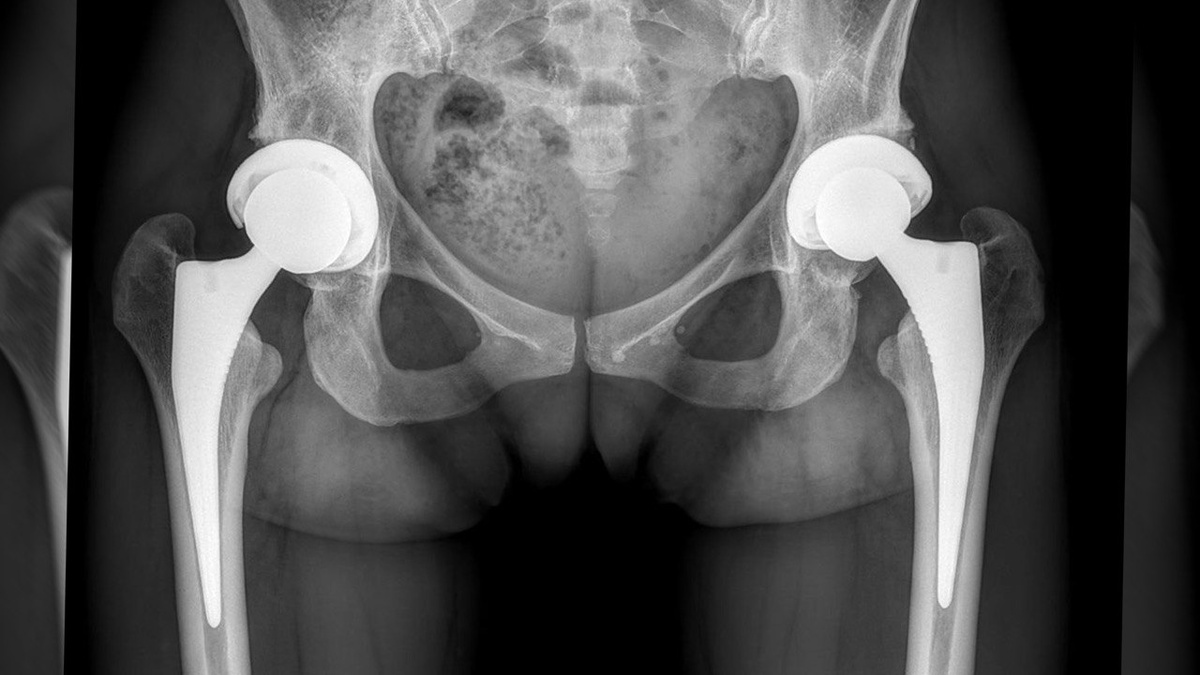

Вторичный коксартроз III стадии, выполнили одномоментное двустороннее эндопротезирование тазобедренных суставов с установкой эндопротезов компании Smith & Nephew. Использовали малоинвазивный доступ. В качестве пары трения выбрана комбинация

«керамика × полиэтилен».

После операции